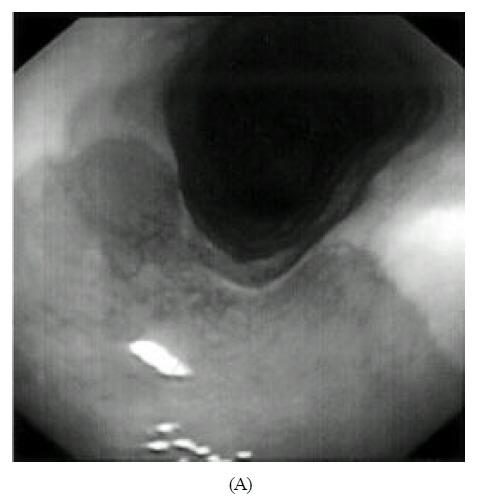

Acid secretion from a heterotopic gastric mucosa in the upper esophagus demonstrated by dual probe 24-hour ambulatory pH monitoring.

Heterotopic gastric mucosa in the upper esophagus is frequently found during endoscopic examination. Although most patients with heterotopic gastric mucosa of the upper esophagus, referred as inlet patch, are asymptomatic, symptomatic patients with complications resulting from this ectopic mucosa have also been reported. Acid secretion by the inlet patch has been suggested in some reports. We report a case of heterotopic gastric mucosa in the upper esophagus, with secretion of acid, demonstrated by continuous ambulatory pH monitoring, and the improvement of pharyngeal symptoms after the use of a proton pump inhibitor.